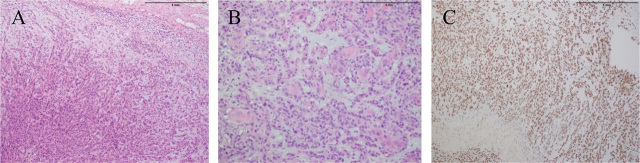

Case presentation: We report a middle-aged female patient, with known case of hypopharyngeal squamous cell carcinoma, who initially showed partial response to chemoradiotherapy but developed cutaneous nodules in the region of the right axilla and bilateral lateral chest wall posterior to the posterior axillary fold. Excision biopsy of one of these nodules showed metastatic squamous cell carcinoma. The patient was again referred to the Oncology Department of INMOL Hospital and her chemotherapy was planned for cutaneous metastasis.